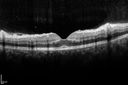

25 year old man with 1 week vision loss 20/16 OD 20/100 OS - CRVO

Heterozyrous for Factor V Leiden - Required 3 years of Lucentis - VA improved to 20/30. Able to stop therapy